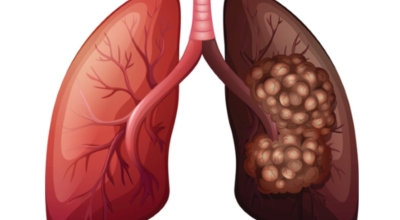

폐암에 대해서

폐에 발생된 악성 종양을 말하며 오랜 기간 흡연해온 남성들에서 발병률이 높고 요즘 들어서 갖가지 환경적인 요인의 영향과 간접흡연으로 흡연하지 않는 여성에서도 많이 발생하고 있답니다. 증상을 느껴 병원을 찾았을 때는 수술하기 늦은 경우가 많아 사망하는 비율이 매우 높은 암입니다. 폐 자체에서 생기거나 다른 장기에서 발생된 암이 폐로 전이되어 나타나기도 하고 특별한 초기 증상이 없는 경우가 많으며 암이 진행된 후에도 일반적인 감기 증상인 기침과 가래 외의 특이 증상이 나타나지않아 증상만으로는 진단이 쉽지 않아요.